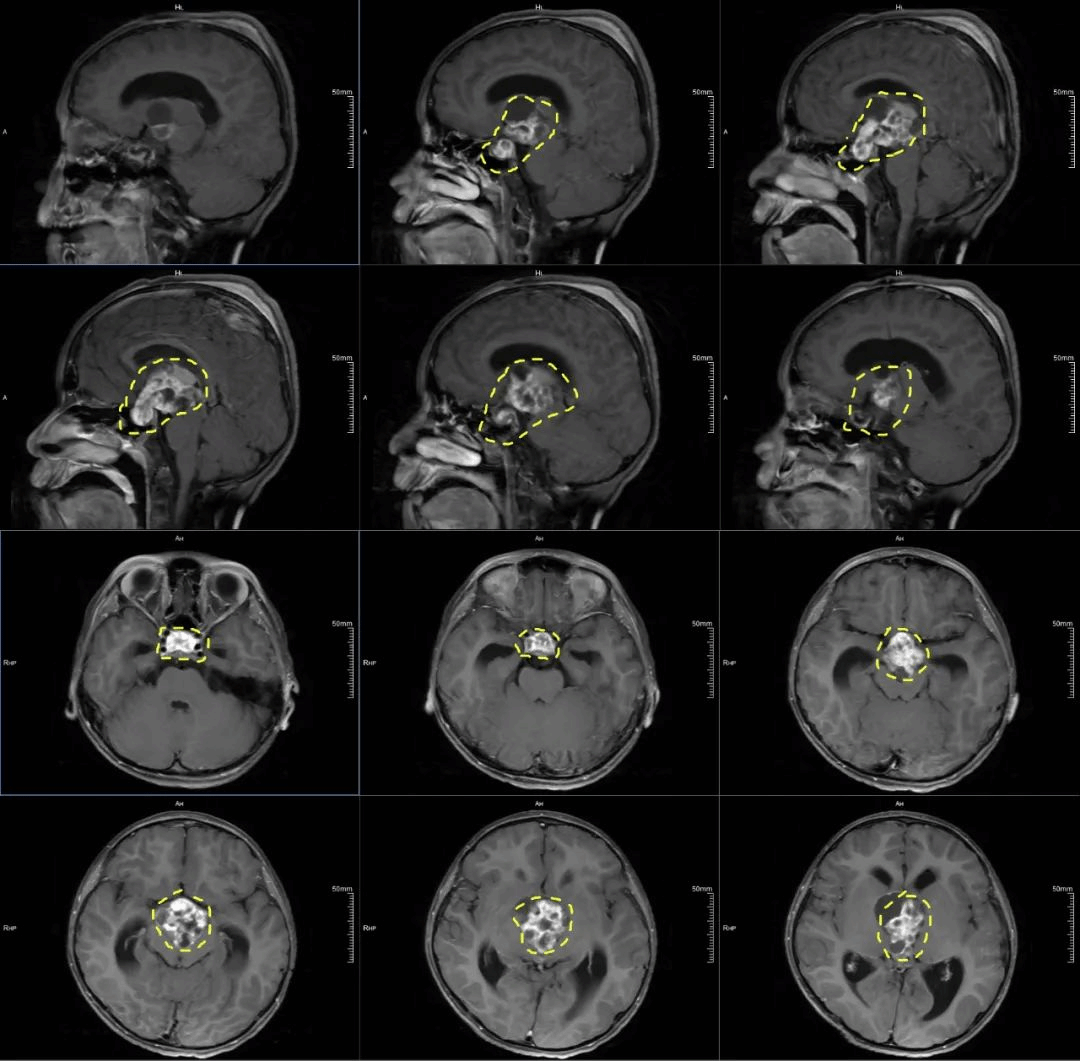

“肿瘤体积很大,从鞍内沿着垂体柄生长,蔓延到第三脑室,并充满整个第三脑室。”纪文元副主任医师说。

术前核磁共振影像图